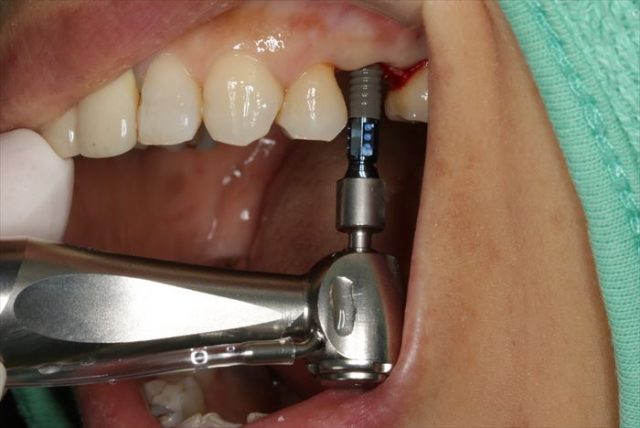

インプラントをモーター埋入している場面です。

埋入を終えました。青いパーツは埋入時用のジグです。

咬合面観です。

近遠心幅が狭いのでポジションの位置決めには緊張します。